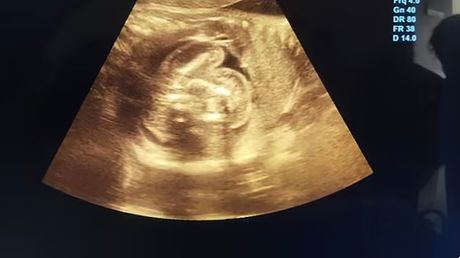

Prošlog meseca, 32-godišnja žena otišla je u lokalnu bolnicu na rutinski ultrazvučni pregled dok je bila u 35. nedelji trudnoće. Iako su prethodni pregledi bili uredni, lekari su u stomaku nerođenog dečaka primetili „dodatnu strukturu sa kostima“.

Dalja ispitivanja otkrila su da su unutar fetusa postojala još dva malformisana fetusa.